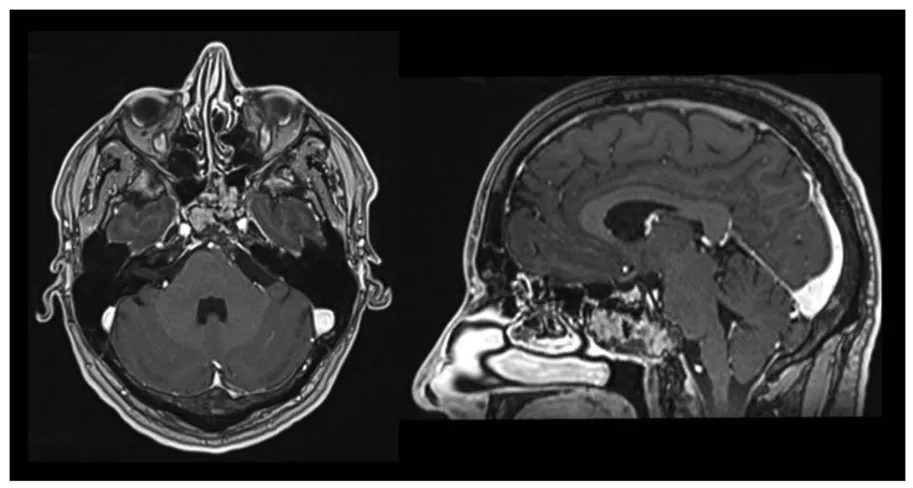

一名33岁男性因进行性加重的颈后部疼痛持续数月就诊。计算机断层扫描发现后颅窝有一枚钙化的轴外病变。磁共振成像确认为岩斜区脑膜瘤(29×39×38毫米),对脑桥和第四脑室产生占位效应,但未见脑积水。综合评估后,团队计划采用右侧单鼻孔经鼻入路进行手术切除。术前对咽升动脉和脑膜垂体干进行了栓塞,术后磁共振成像证实病灶成功去血管化。

图1. A和B,脑部计算机断层扫描及增强磁共振成像的轴位视图,显示一强化不均匀的低位左侧岩斜区脑膜瘤。C,术前咽升动脉和脑膜垂体干的栓塞。D,磁共振成像矢状位视图显示岩斜区脑膜瘤的部分去血管化。

图2. 术前栓塞后,采用稳态构成干涉序列的多平面重建磁共振成像,显示脑膜瘤与神经血管结构的关系。BA,基底动脉;JT,颈静脉结节;Opt. Tract,视束;PCM,岩斜区脑膜瘤;SS,蝶窦;V,第五对颅神经;VI,第六对颅神经;VII/VIII,第七和第八对颅神经。